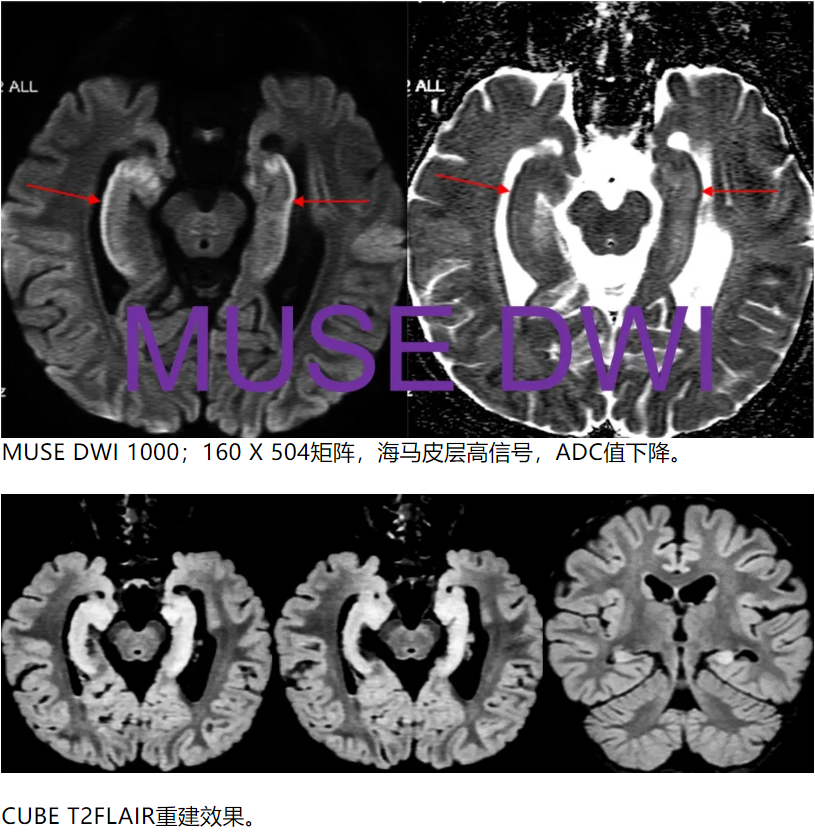

除此之外,海马的信号怪怪的,是什么?所以,我们加扫海马矢状位小视野弥散。

•Sag FOCUS DWI 1000,FOV = 22 × 8.8cm,2.0 / 0.0 mm

海马最外层呈弥散受限表现,但是总感觉雾里看花,并不清晰。我们还能做什么?